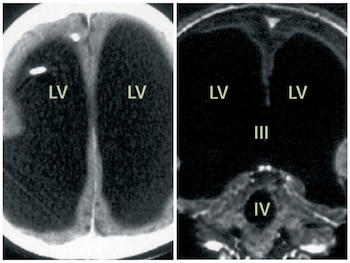

Tras analizarle un escáner cerebral, los médicos descubrieron que su cerebro ocupaba el 10% de su cavidad craneal. El resto estaba lleno de líquido cefalorraquídeo.

Sin embargo, con los años, el líquido continuó acumulándose de manera crónica, comprimiendo progresivamente el cerebro hasta dejarlo reducido a una lámina delgada pegada a las paredes del cráneo.

Los exámenes de las imágenes realizadas en 2003 mostraron una dilatación extrema de los ventrículos cerebrales, un adelgazamiento significativo de la corteza cerebral y la presencia de un quiste en la fosa superior.

Los médicos concluyeron que se trataba de un caso de hidrocefalia no comunicante, probablemente causada por una obstrucción en el foramen de Magendie, una pequeña apertura por donde debería circular el líquido cefalorraquídeo.